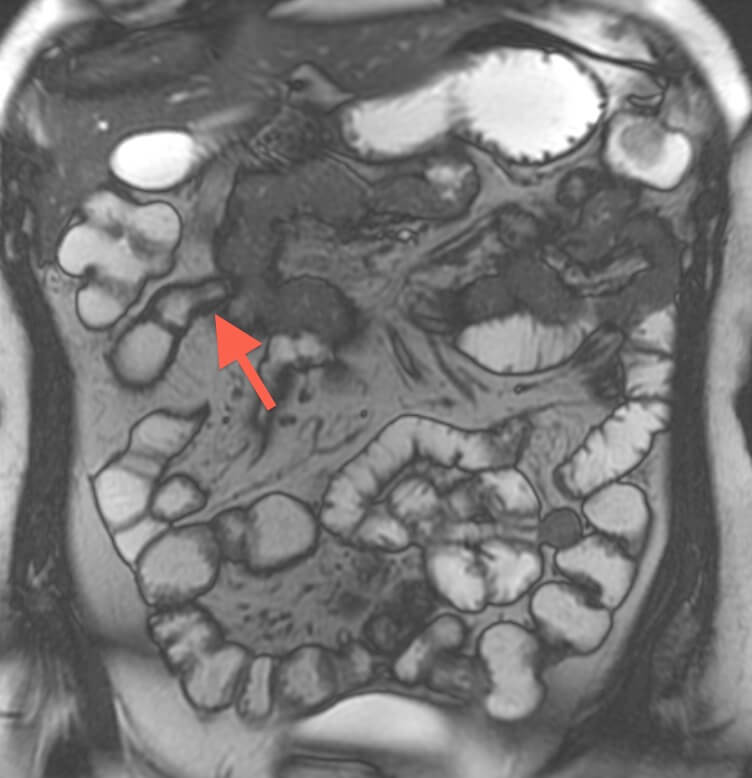

MR enterography is valuable for determining extent of inflamed bowel, discriminating between active inflammation and chronic fibrosing disease, detecting fistulae, and detecting strictures. Additionally, MRI can provide excellent delineation of the course of perianal fistulas, including relationships to sphincters and levators.

Before undergoing MRI to evaluate the bowel, one drinks a little over one quart of a fluid that helps to distend the bowel, and an intravenous catheter is placed so that intravenous contrast can be administered.